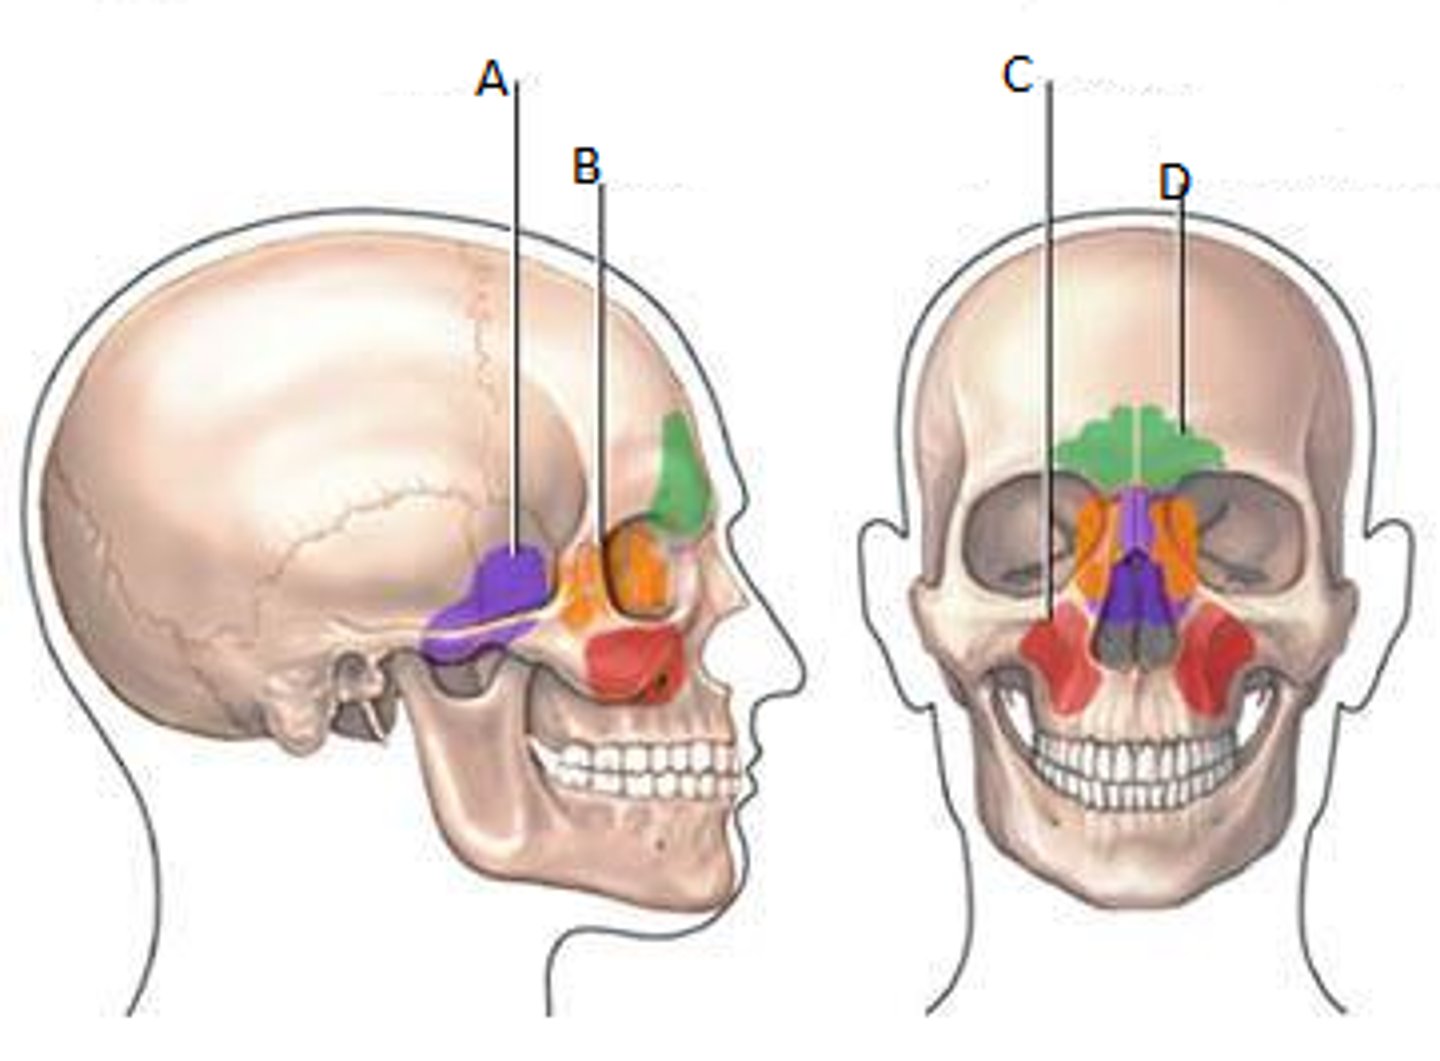

Frontal sinuses

Green

Sphenoid sinuses

Orange

Ethmoid sinuses

Purple

Maxillary sinuses

Red